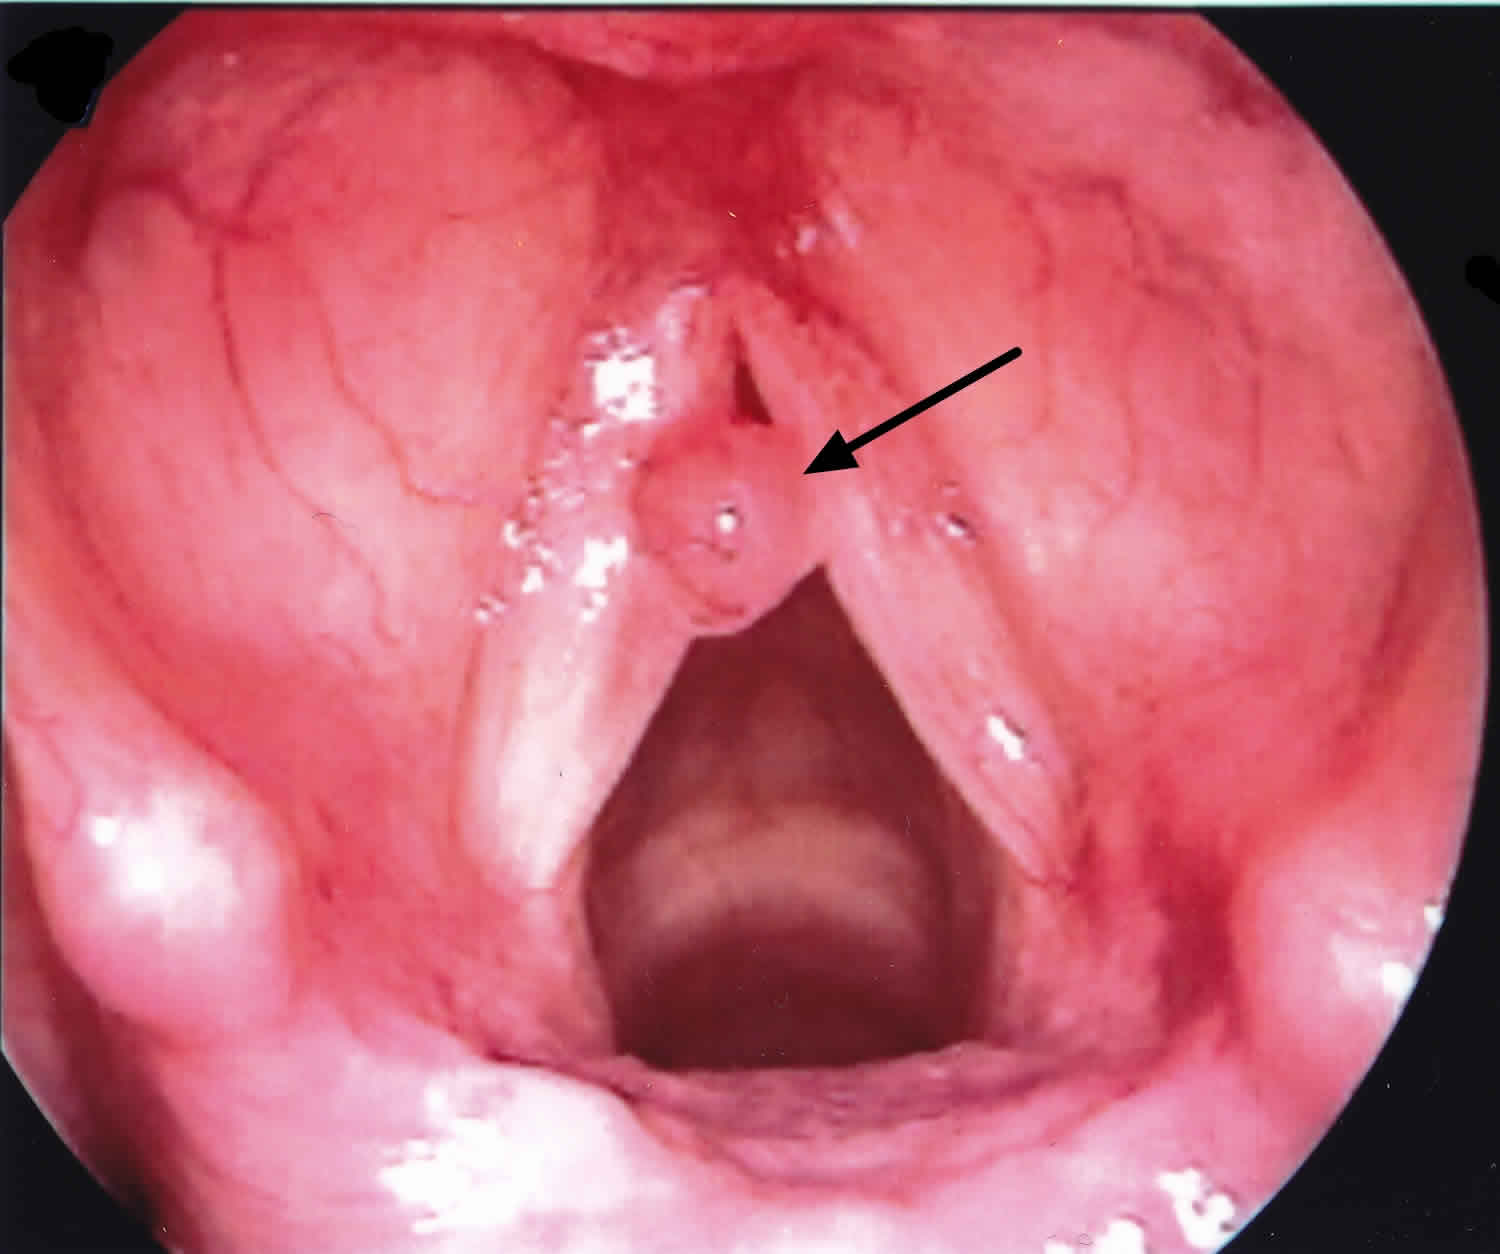

Web if you're experiencing hoarseness, your voice can sound breathy, raspy, or strained, according to the national institute on deafness and other communication. Web the larynx, also known as the voice box, is an organ in your throat that houses the vocal cords, two flaps of tissue that move to allow breathing and vibrate to. Cheering at sporting events, speaking loudly in noisy situations, talking for too long without resting your voice, singing loudly, or.

Still, symptoms depend on the lesion’s size and how much it interferes with your vocal cords. Web laryngitis is an inflammation of the larynx, the area that houses your vocal cords. Inability to speak or make sound hoarseness throat pain problems swallowing diagnosis the doctor will ask about your symptoms and health history.